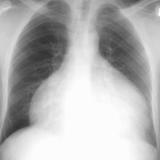

Case 7b

Peric effusion

Date: 02/25/2013

Views: 3182